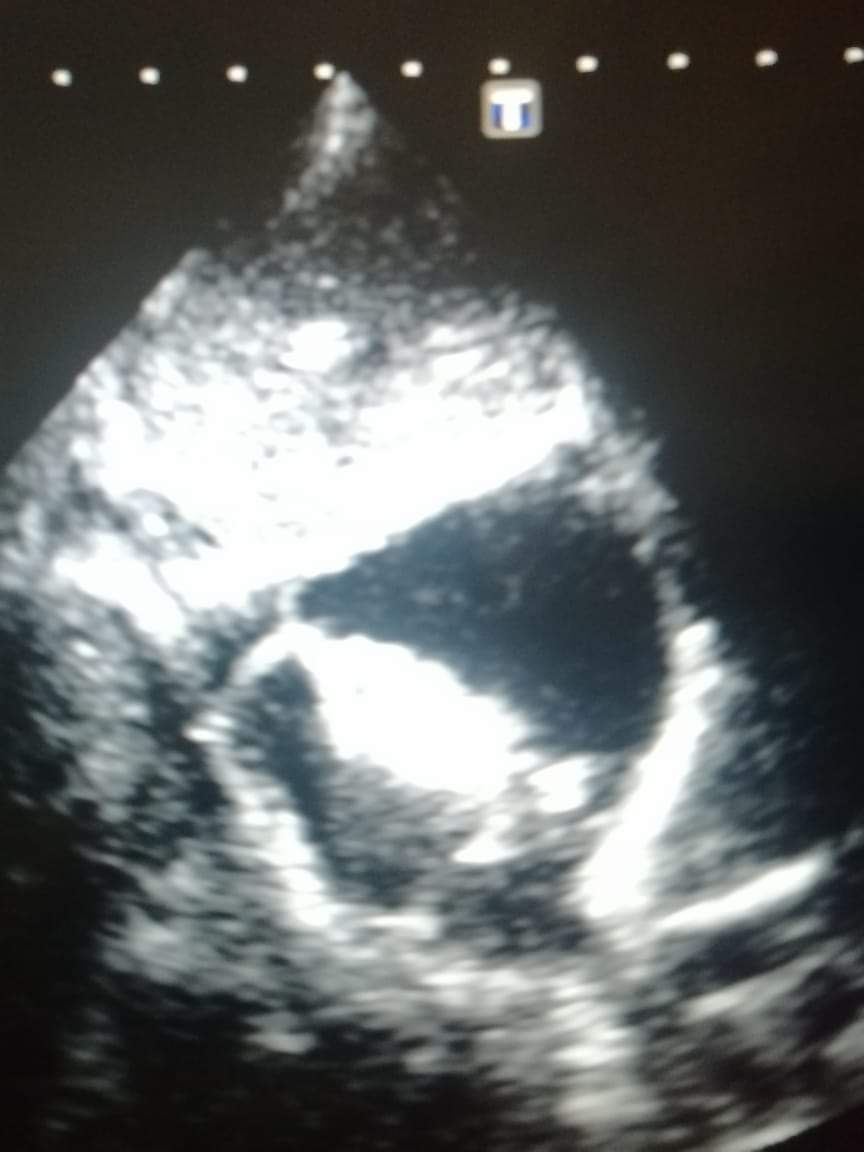

حيث أجرى د. داني يوسف المتخصص في امراض القلب عند الاطفال وفريقه الفني عمليه لطفلة تبلغ من العمر سنتين ونصف وتزن ١٠ كلغ وهي تعاني من تشوه قلبي منذ الولادة

(ASD CLOSURE)

وتحتاج الى عملية جراحية لاغلاق الفتحة بين الأذين الأيمن والأذين الأيسر وقد اجري هذا العمل الطبي التداخلي interventional therapy دون إستخدام الجراحة عبر تقنية البالون المساعد من أجل وضع الجهاز في مكانه الصحيح بدل من اجراء عملية جراحية لتعتبر هذه العملية من العمليات النادرة لهذه المرحلة العمرية حيث تنفرد مستشفى الرسول الاعظم بأطباء متخصصين ينفذون هذا النوع من العمليات ولجميع الاعمار